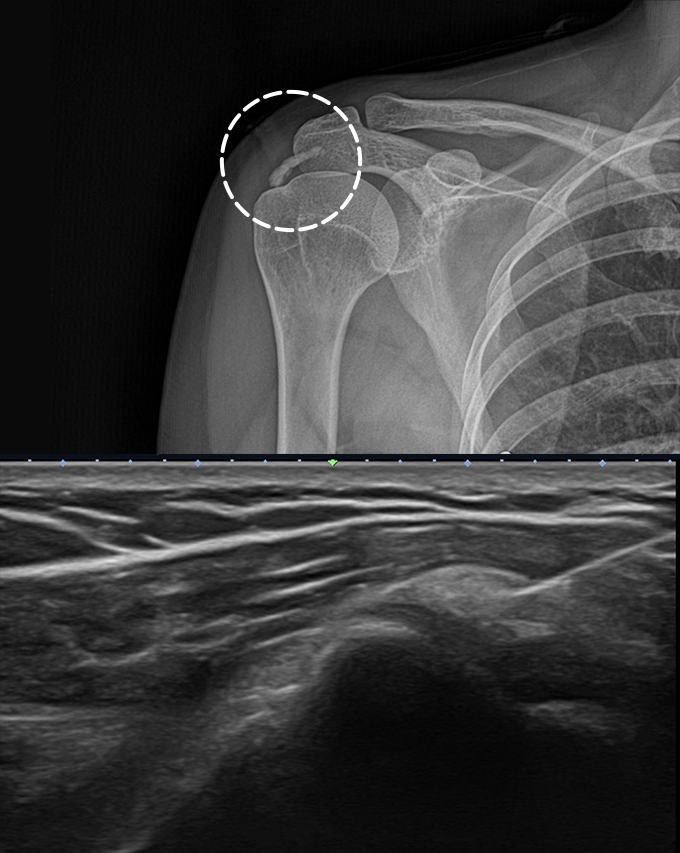

석회성건염 환자를 위한 비수술적 치료법으로, 초음파로 석회의 정확한 위치와

크기를 파악한 후 얇은 바늘로 석회를 직접 제거하는 시술입니다.

프로정형외과에서는 20년 이상의 풍부한 어깨치료 경험을 가진 의료진이 초음파로

정확한 석회 위치를 파악하고 정교하게 시술을 진행합니다.